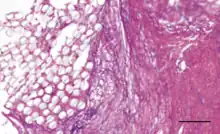

The Ligament Advanced Reinforcement (LARS) is a leading artificial ligament in ACL repair surgery. They are made of polyethylene terephthalate (PET).[3] They consist of an intraosseous and an intra-articular portion. The intraosseous section consists of longitudinal fibers bounded by a knitted transverse structure. This knitted structure can help prevent deformation and abrasion.[5][11] The intra-articular portion is made of longitudinal fibers pretwisted at a 90 degree angle. This section is designed to resist fatigue and promote tissue ingrowth.[5] Leeds Keio ligaments consist of a polyester mesh structure. It seeks to mimic the mechanical properties of the native ACL. The porous nature of the ligament can promote tissue ingrowth which has been shown to improve mechanical properties.[5] The PGA Dacron artificial graft consists of 75% braided biodegradable polyglycolic acid and 25% permanent Dacron thread.[11] The Kennedy LAD artificial ligament is made of polypropylene ribbons. It is designed to promote tissue ingrowth and the progressive transfer of load onto the new ligament.[10]

The native ACL of a human has a tensile strength on the order of kilonewtons,[3] and an elongation at failure of approximately 10%.[10] The mechanical properties of the native ACL vary throughout the human population. The strength of a child's ACL tends to be greater than that of an adult.[10] PGA Dacron artificial ligaments have an ultimate tensile strength near 3500 N and a mean ultimate elongation of approximately 20%.[10] Kennedy LAD ligaments have a tensile strength at failure of approximately 1500 N and an approximate stiffness of 50 N/mm.[10] Leeds-Keio artificial ligaments have an ultimate tensile strength near 2000 N and a stiffness around 250 N/mm after tissue ingrowth.[10] LARS artificial ligaments have varying mechanical properties depending on the amount of fibers used. A higher gauged ligament will have a greater tensile strength. During testing, a 60 gauge LARS ligament exhibited an ultimate tensile strength of 2500 N while a 120 gauge ligament exhibited a tensile strength of 5600 N.[5][12] The ingrown tissue has been shown to improve viscoelastic properties and reduce friction.[5]

Coatings have been added to artificial ligaments to improve their biocompatibility. 58S bioglass and hydroxyapatite coatings have been shown to improve osseointegration and cellular activity in vitro and in animal studies[3] when deposited onto PET ligaments using the soaking method.[2][3] Hydroxypropyl cellulose surface treatments have been shown to improve osseointegration for PET ligaments in animal studies.[2] Uncoated PET is hydrophobic, so coatings are designed to improve hydrophilicity.[3] Hyaluronic acid coatings can reduce hydrophobicity and have been shown to reduce scar tissue formation and inflammation in vivo.[3] Hyaluronic acid and chitosan composite coatings can be deposited onto artificial ligament surfaces by the layer-by-layer technique, and they have been shown to enhance new bone formation at the ligament interface in mice.[9] The chitosan is used to reduce hydrophobicity and improve osseointegration and mineral deposition, while the hyaluronic acid promotes cell differentiation and growth.[9] Poly(sodium styrene sulfonate) coatings have been shown in animal studies to improve knee functionality and mimicry of the native ACL.[2][13]